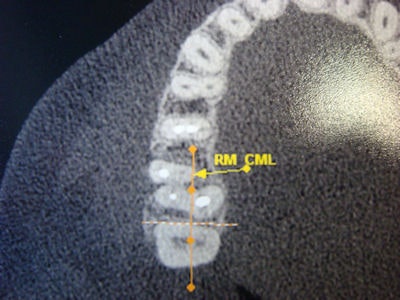

![]() ![]() |

| Left, a cone-beam CT lateral view showing a fractured root canal in a first maxillary premolar. Right, a cone-beam CT occlusal view showing root canals. Images courtesy of Flares Baratto Filho, Ph.D. |